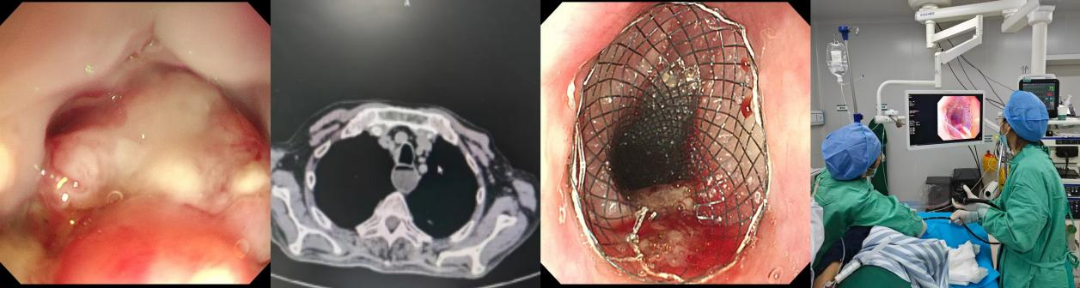

入院检查显示:食管中下段癌合并纵隔多发转移,从门齿26厘米至40厘米,肿瘤几乎侵及整个食道,食管壁全周溃烂易出血。医院迅速组织多学科会诊,将患者转入消化二科。科主任刘元综合研判后,决定采用“双支架置入术”解除食管长段狭窄,帮助患者恢复进食。

2月27日下午4时, 刘元主任带领团队为患者实施手术,仅用不到15分钟,两枚支架精准置入狭窄的食管中下段。术后患者无任何不适,当天即可饮水进食半流质,精神状态明显好转。患者家属感慨:“兜兜转转一大圈,没想到在家门口解决了大问题。”